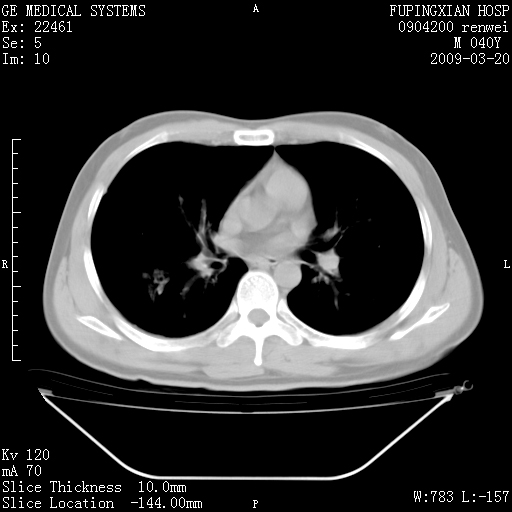

标题: CT18920:平时体健,体检时发现以下问题。 [打印本页]

标题: CT18920:平时体健,体检时发现以下问题。

单侧肺气肿表现,原因?   特发性或先天性可能

右肺气肿。

右肺局限性肺气肿

右肺局限性肺气肿。

右肺局限性肺气肿,有无呛咳史?

右肺局限性肺正常

双肺弥漫磨玻样改变,肺纹理增重,考虑早期间质纤维化伴局部阻塞肺气肿,[考虑黏液栓]

右肺局限性肺气肿;[考虑黏液栓]所致。

透明肺

双肺弥漫磨玻样改变,右肺局限性肺气肿。病人没有症状?

考虑间质性肺炎伴右侧局限性肺气肿,

右肺局限性肺气肿;[考虑黏液栓]所致

先天性支气管闭锁

右肺局限性肺气肿,原因?先天支气管闭锁?粘液栓?